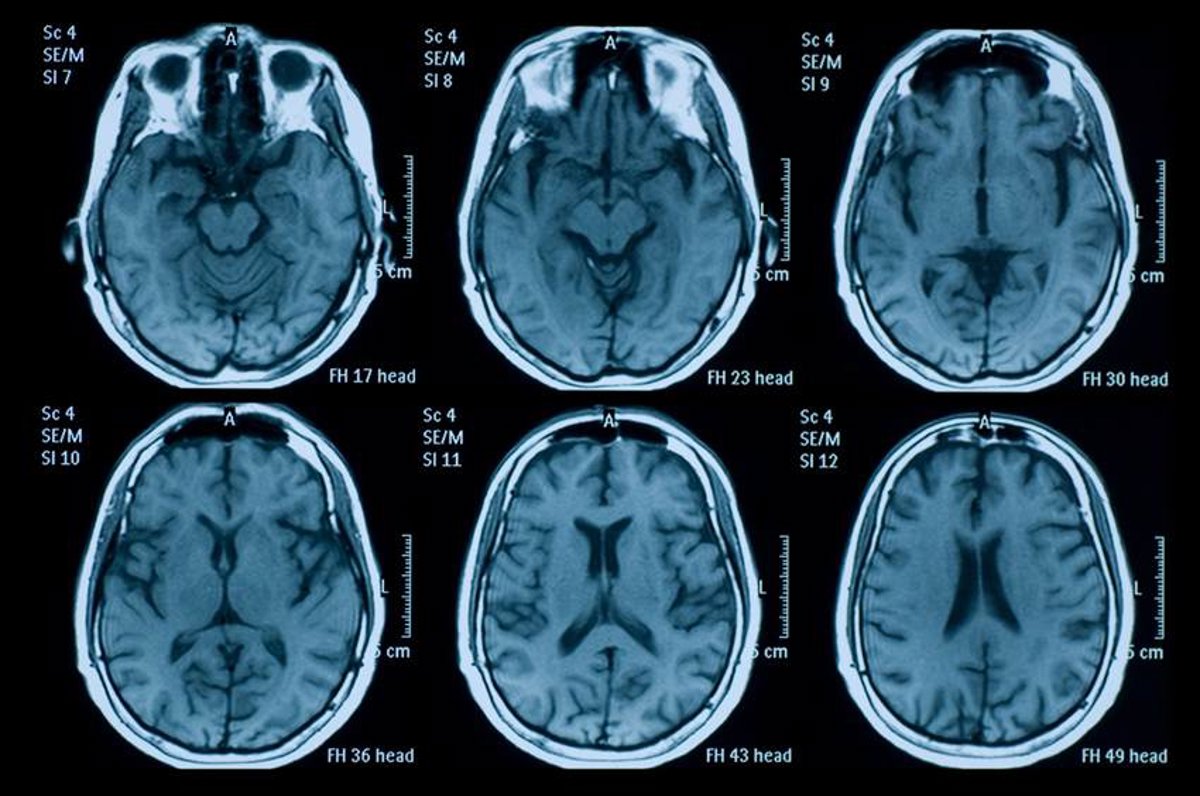

El estudio, publicado en la revista 'EMBO Molecular Medicine', ha mostrado como este péptido formado por cuatro aminoácidos se dirige específicamente a las zonas dañadas del cerebro tras ser inyectado por vía intravenosa poco después de la lesión, "atraído" por las glicoproteínas, que están presente en mayor cantidad en las zonas lesionadas tras un traumatismo.

CAQK se acumula en las zonas marcadas por la proteína y logra reducir tanto la inflamación como la muerte celular y el daño en el tejido cerebral, mejorando también la recuperación funcional, sin mostrar toxicidad aparente en ratones, lo que abre "nuevas posibilidades" a tratar zonas lesionadas del cerebro.